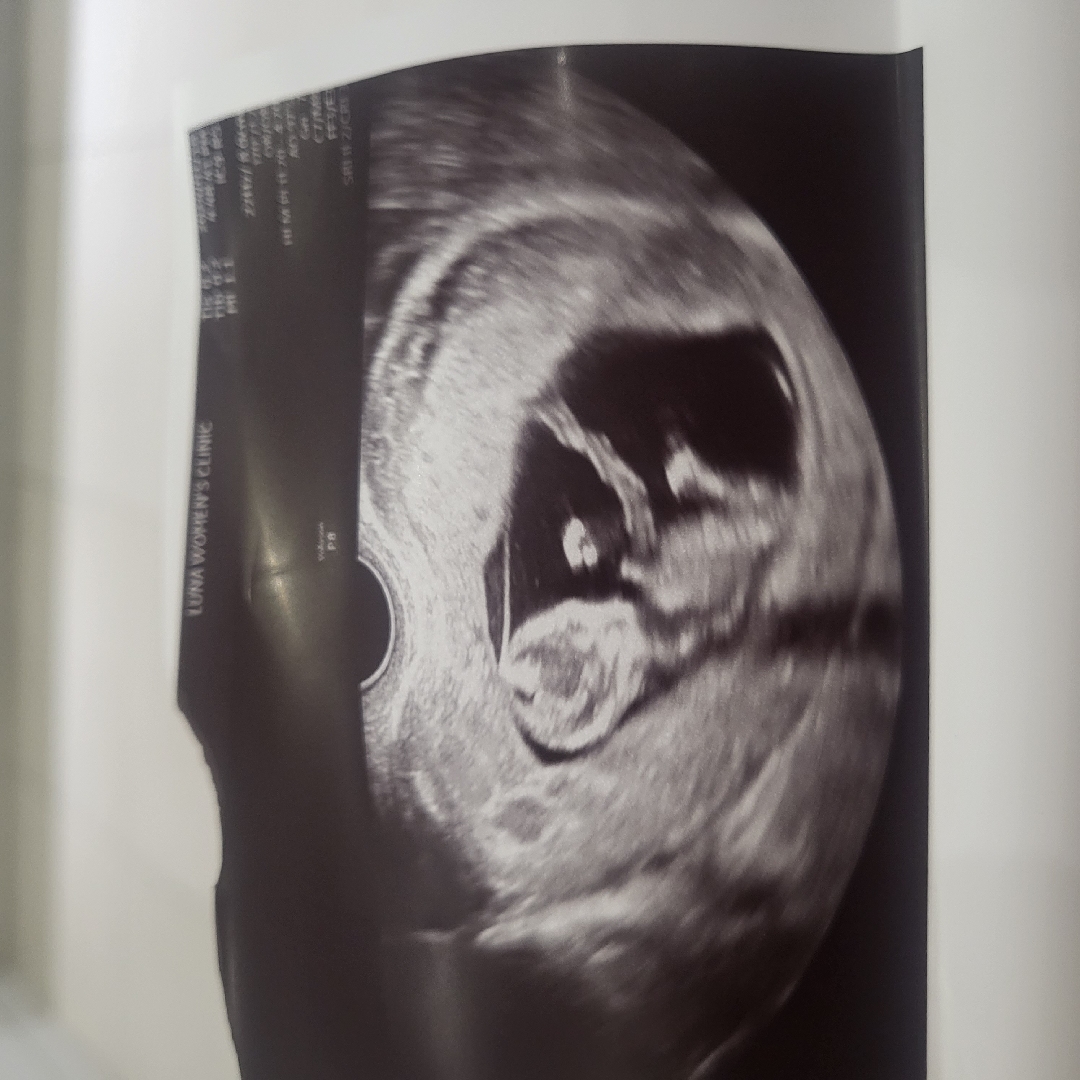

현재11주, 12주각도법으로 봤을때 아들, 딸?!

현재 11주이고 정기검사는 다음주인데 입덧약도 탈겸 서브병원에서 초음파 보고왔어요! 아직 12주는 아니지만... 12주 각도법으로 봤을때는 아들일까요? 딸일까요? 둘다 너무 좋은데 막상 또 엄청 궁금하네요ㅎㅎㅎ